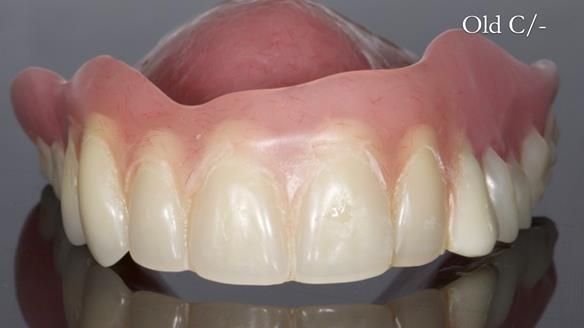

- Current complete upper denture had many technical problems. Poor retention, support, stability and tissue fit.

- Complete upper dentures – metal reinforced. David wanted this

Interestingly we found that the upper complete denture when finished and fitted didn’t have good enough retention for David’s satisfaction. It was relined by adding compound to the buccal flanges – to almost overextend into the sulcus to ‘create’ a sulcus, followed by using a light bodied silicone impression material. This improved the function of the C/-considerably. A lower Scandinavian hygienically designed lower RPD was also provided which helped with occlusal stability and reseating the upper denture – further improving the fit.